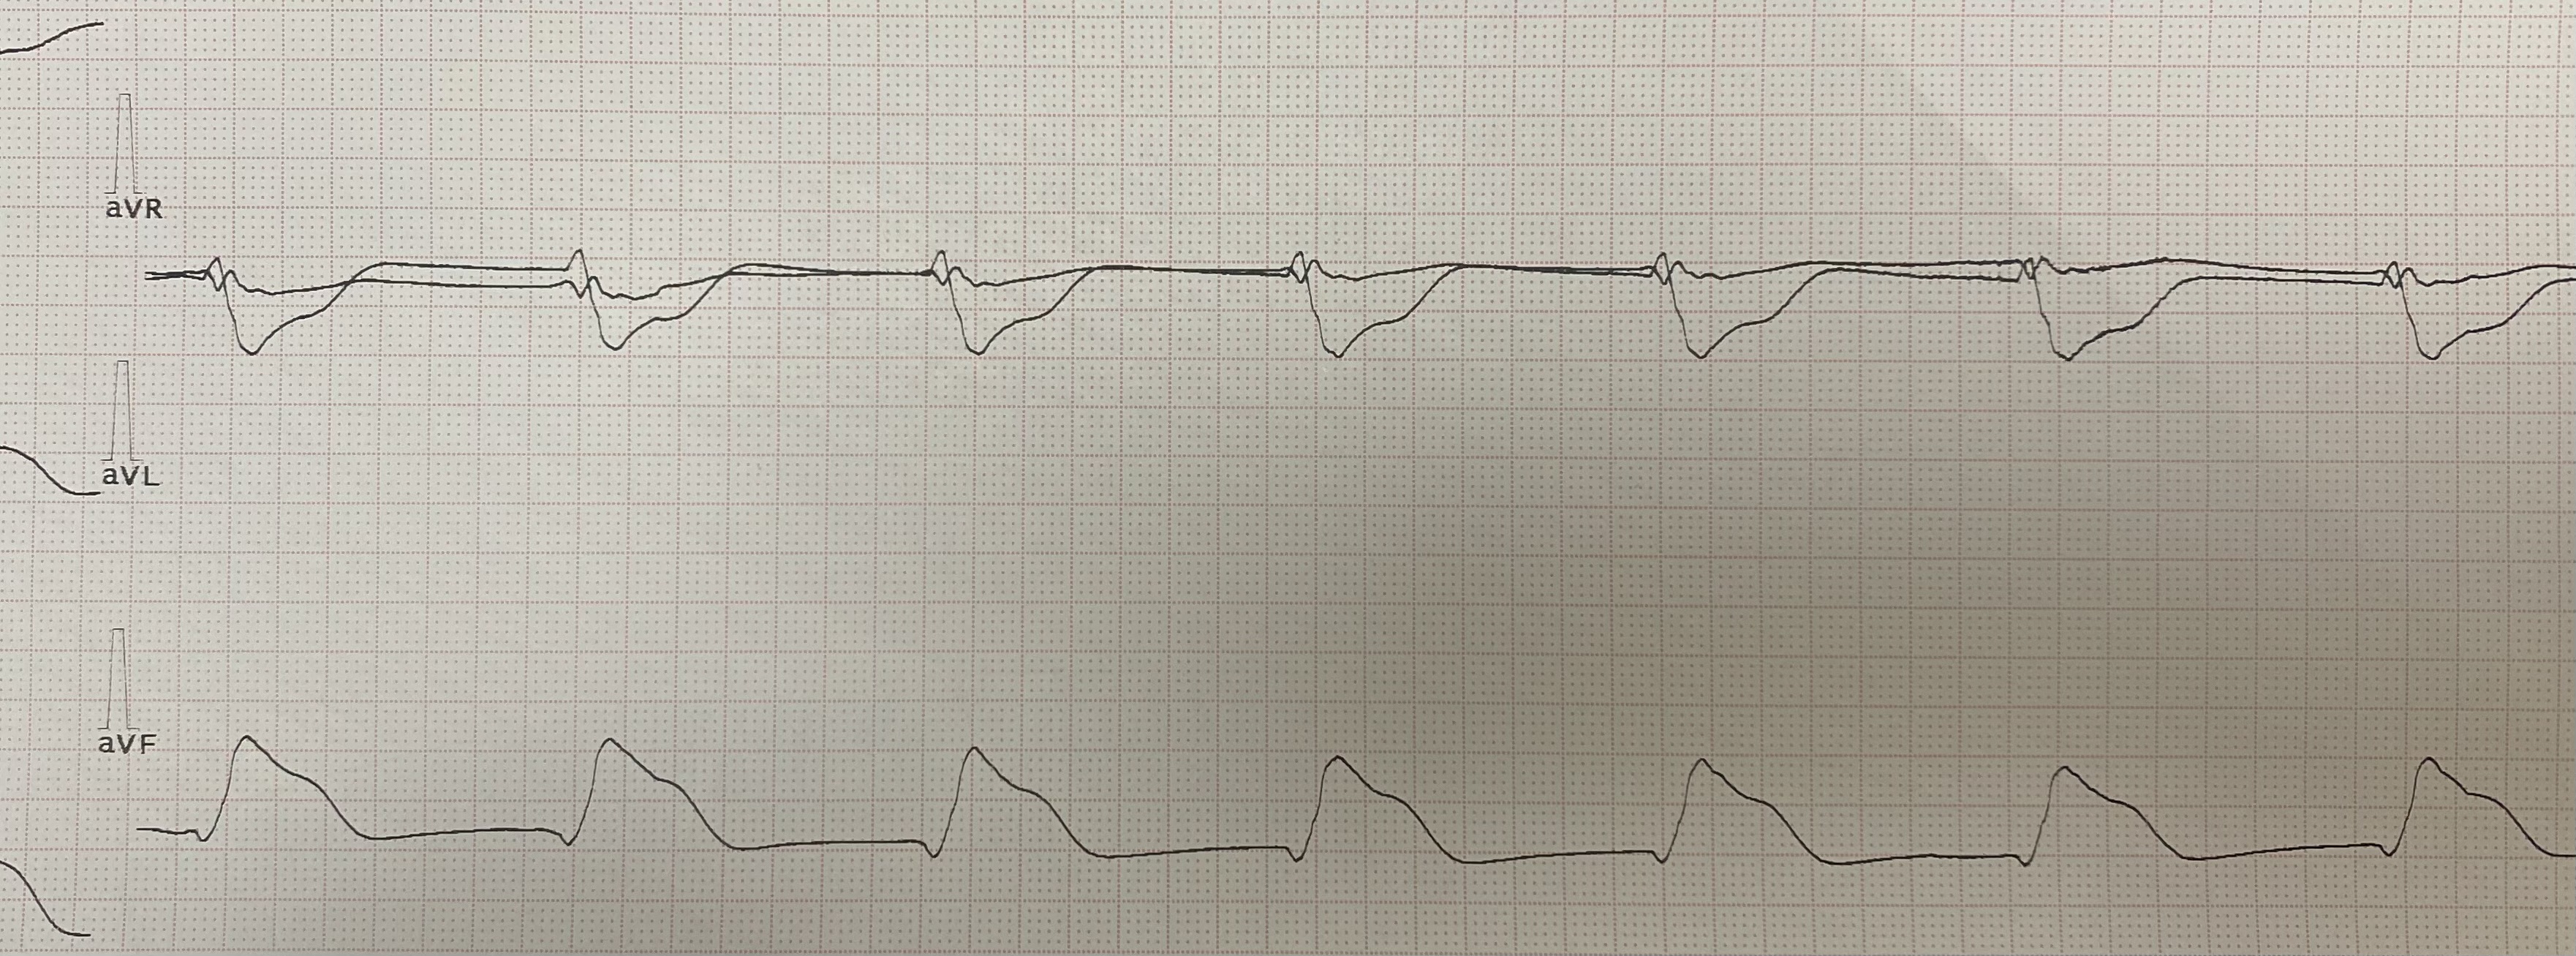

Больная на фоне приема соталекса стала ещё ритмонорм принимать. Всё прошло без стимуляции. Ритм АВ узла с БЖБ

Изображение

Обсуждалось здесь viewtopic.php?f=11&t=11113&p=107225#p107225